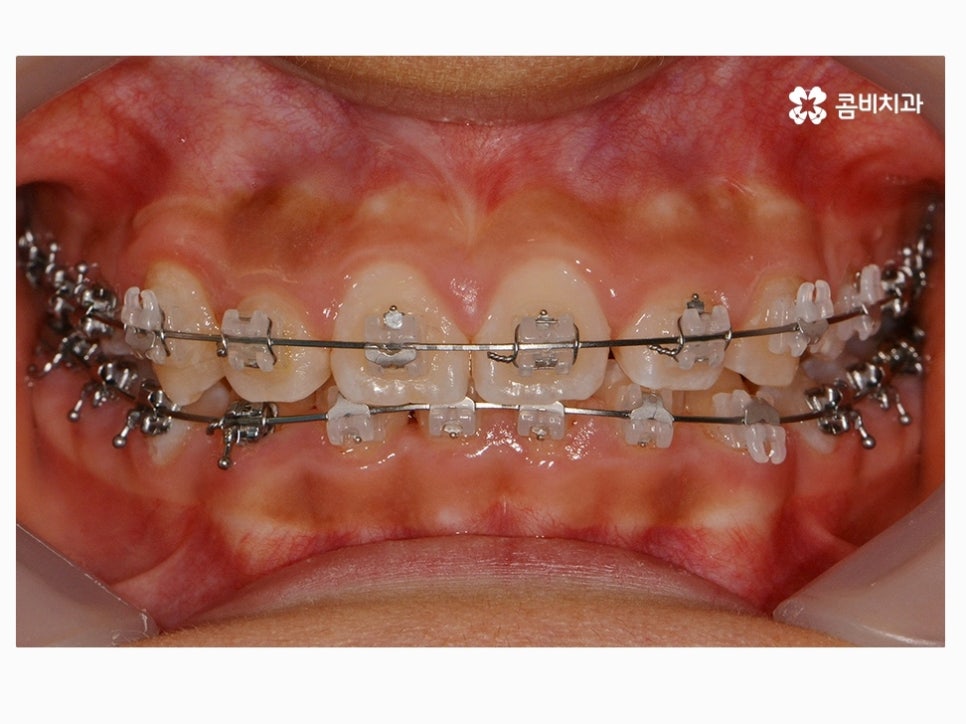

위 환자분께서 사용하신 장치는 클리피씨로 자가 결찰 장치이며

초기 통증이 줄어들고 관리가 용이하며 시술 기간을 단축시킬 수 있다는 장점이 있어요.

요즘은 이처럼 세라믹 재질을 활용하여 심미성은 높이고

교정 과정이 보다 효율적인 장치가 많이 사용되고 있는데요.

사춘기에는 교정 장치에 대한 심미적인 부담감을 크게

느끼거나 통증에 대한 걱정으로 치과에 대한 거부감을 드러내는

경우도 많지만 특히 부정교합의 경우에는 나이가 들수록

치아의 심미성 외 건강적인 부분에서도 문제가 커질 수 있기

때문에 되도록 빠른 치료를 권유 드리고 있어요.